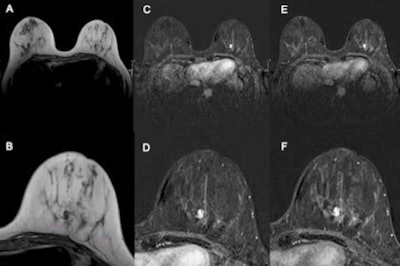

The aim of the researchers was to evaluate the diagnostic performance of untrained residents using the Kaiser Score compared with offsite radiologists experienced in breast imaging using only MR BI-RADS. Three offsite, board-certified radiologists experienced in breast imaging interpreted MRI scans according to the MR BI-RADS scale.

The same studies were read by three residents in radiology without prior training in breast imaging using the Kaiser score. All readers were blinded to clinical information, and histology was used as the gold standard.

A total of 80 women (median age, 52 years) with 93 lesions (32 benign, 61 malignant) were included in the study. The individual within-group performance of the three expert readers (area under curve [AUC], 0.723-0.742), as well as the three residents, was equal (AUC, 0.842-0.928). But the rating of each resident using the Kaiser score significantly outperformed the experts' ratings using the MR BI-RADS scale.